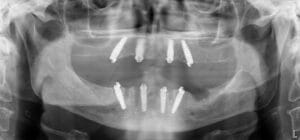

We use a CBCT (cone beam CT) scan alongside digital impressions and photography to create a precise 3D model of your mouth. This allows us to plan your implant placement virtually.

A dental navigation system is a computer-aided tool that guides dentists during implant placement. It merges CBCT scans with digital impressions to create a virtual 3D model of your mouth. The system then provides real-time guidance so the implant is positioned at the exact angle, depth, and location planned in advance. This improves accuracy, reduces invasiveness, and ensures long-lasting results compared with freehand placement.

Yes. Studies consistently show that navigated dental implants placed with a 3D navigation system are more accurate than freehand implants. The system reduces margin of error, ensures correct angulation, and decreases surgical time. For patients, this means less discomfort, faster healing, and more reliable outcomes.